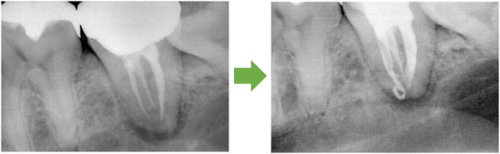

根の先に病巣ができています。

かぶせ物と土台を外します→根の管に詰まっている薬を外します→再び根の管を拡げます